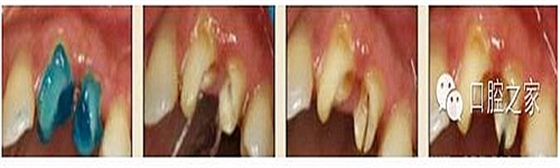

圖3:根管內(nèi)殘留物

圖4:超聲去除根管殘留物?! ?p>根管壁殘留物的存在直接影響著纖維樁的粘接和固位,是纖維樁脫落的主要原因之一。由于圓形的根管鉆和根管形態(tài)不完全一致,終鉆預(yù)備完成后大多情況下樁道側(cè)壁會有不同程度的牙膠和封閉劑等殘留物附著(圖 3)。因此,建議X線檢查根管預(yù)備情況,選用超聲潔牙機更換較細工作尖進入根管,徹底去除樁道根管壁上附著的殘留物(圖4)。使用根管銼去除殘留物時,很難清除干凈;禁止使用牙膠溶劑如丁克除、氯仿等有機溶劑去除殘留物,以免破壞根尖區(qū)牙膠的封閉,或有機溶劑粘附于根管壁形成蠟?zāi)ざ绊懻辰印?#pages##